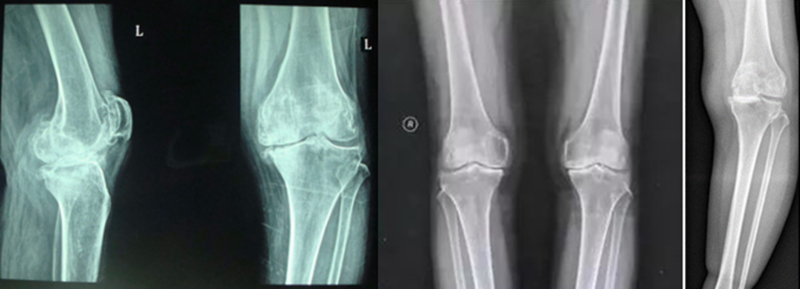

病例1:46岁,滑雪运动员,多发韧带伤,内翻畸形膝关节疼痛,开式截骨后二月全负重行走,膝关节疼痛缓解

病例2:男性,19岁,因发现右膝关节内翻、过伸畸形伴跛行5年(左侧膝关节也有类似畸形,暂时无症状)。于2006年7月就诊,其母亲也有类似病史。查体:右膝关节内翻畸形约15度,应力下过伸约20度,内翻及外翻时膝关节均有松动感,Lanchman试验(+)。无负重下X片示:右膝关节内翻畸形约15度,胫骨平台无后倾,倒呈前倾13º。膝关节MR示:右膝内侧股骨及胫骨软骨面已有缺损并囊性变。诊断:先天性膝关节内翻畸形(Blount病)。

术前X线可见右膝关节内翻畸形约15°,胫骨平台前倾畸形13°

术前膝关节MR示:右膝内侧胫、股骨骨软骨面已有缺损并囊性变

应力位过伸畸形明显

术后6月X片示右膝内翻、前倾畸形已矫正,胫骨截骨处愈合,腓骨未愈合,但无症状。